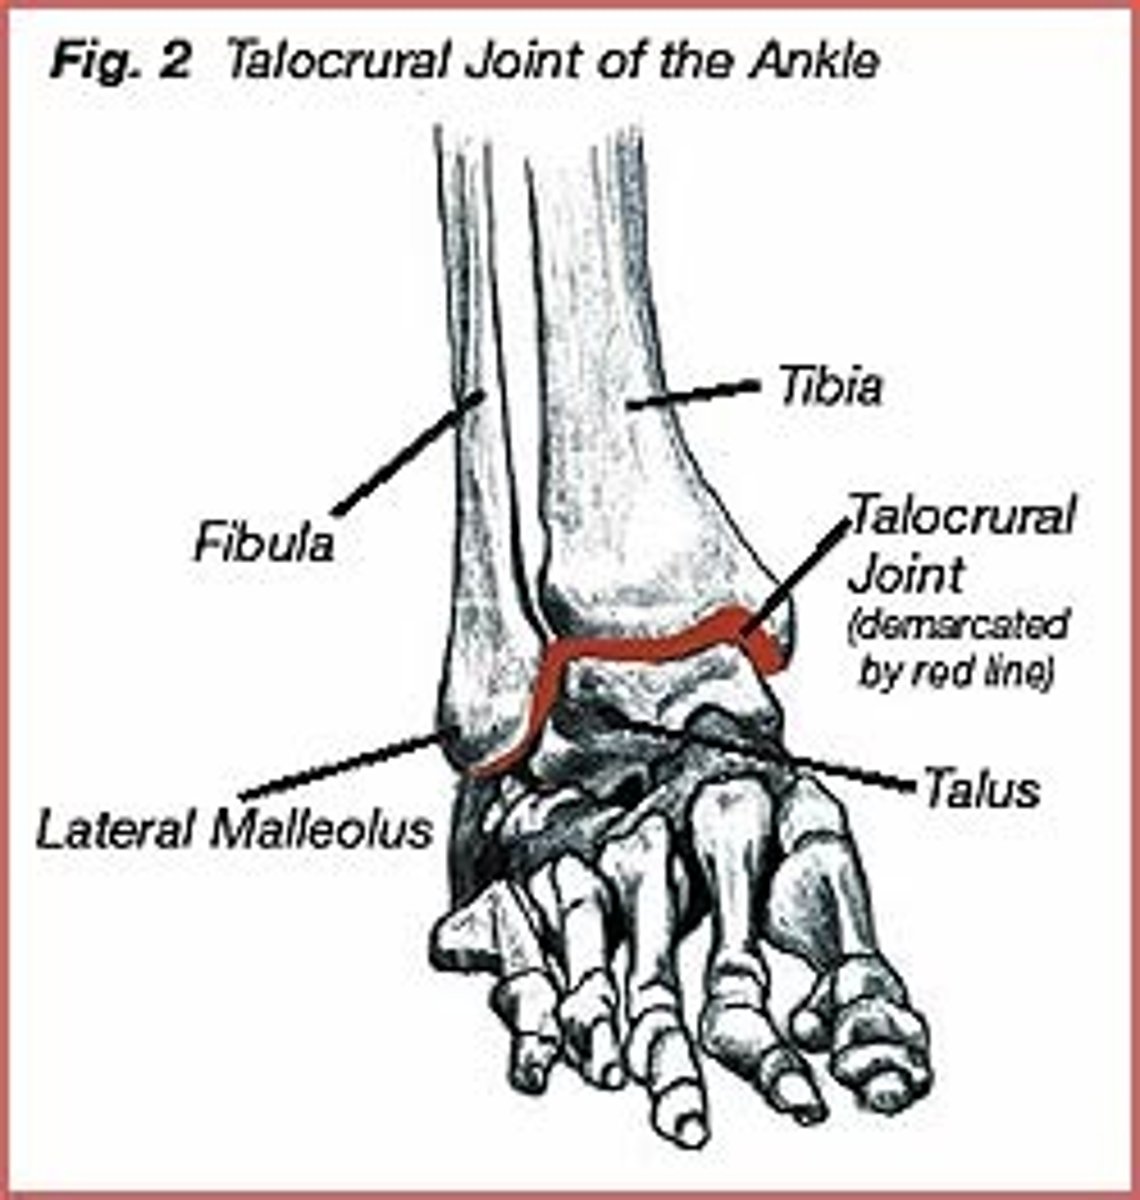

Bones that comprise the ankle (3)

Tibia

Fibula

Talus

Joints of the ankle (3)

Talocrural joint (primary)

In the talocrural joint, is the talus the convex or concave component?

Talus is CONVEX in the talocrural joint

What is the concave component of the talocrural joint?

The tibia and fibula

What type of joint is the talocrural joint? (specific classification based on shape)

Mortise joint